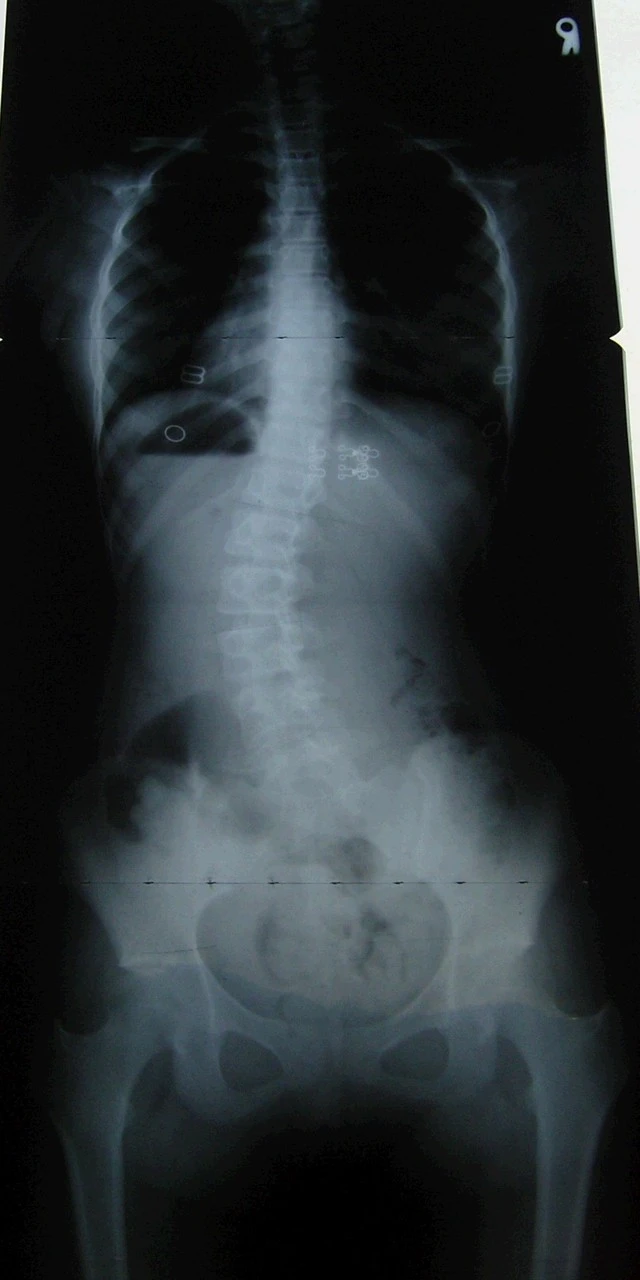

척추 측만증(scoliosis)

척추가 10도 이상 휘어진 상태를 측만증이라고 한다.

실제로는 척추가 3차원적으로 틀어져 있다.

구조적 측만증은 골격이 비틀려 외모와 X레이 검사에서 확실한

차이가 있다.

척추의 일부분이 휘어지거나 척추 전체에서 나타난다.